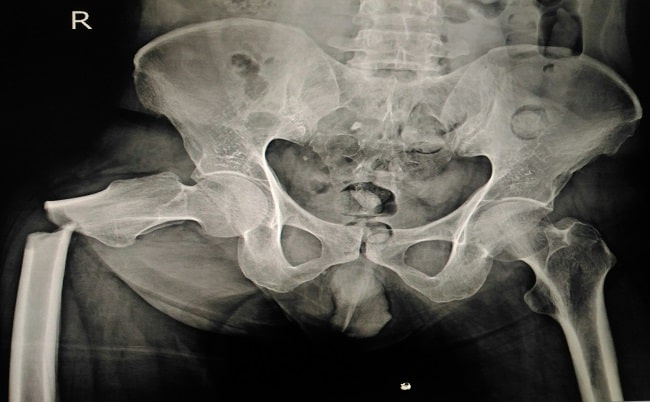

Broken Pelvis Body Cast

Broken Pelvis Body Cast 116 photos